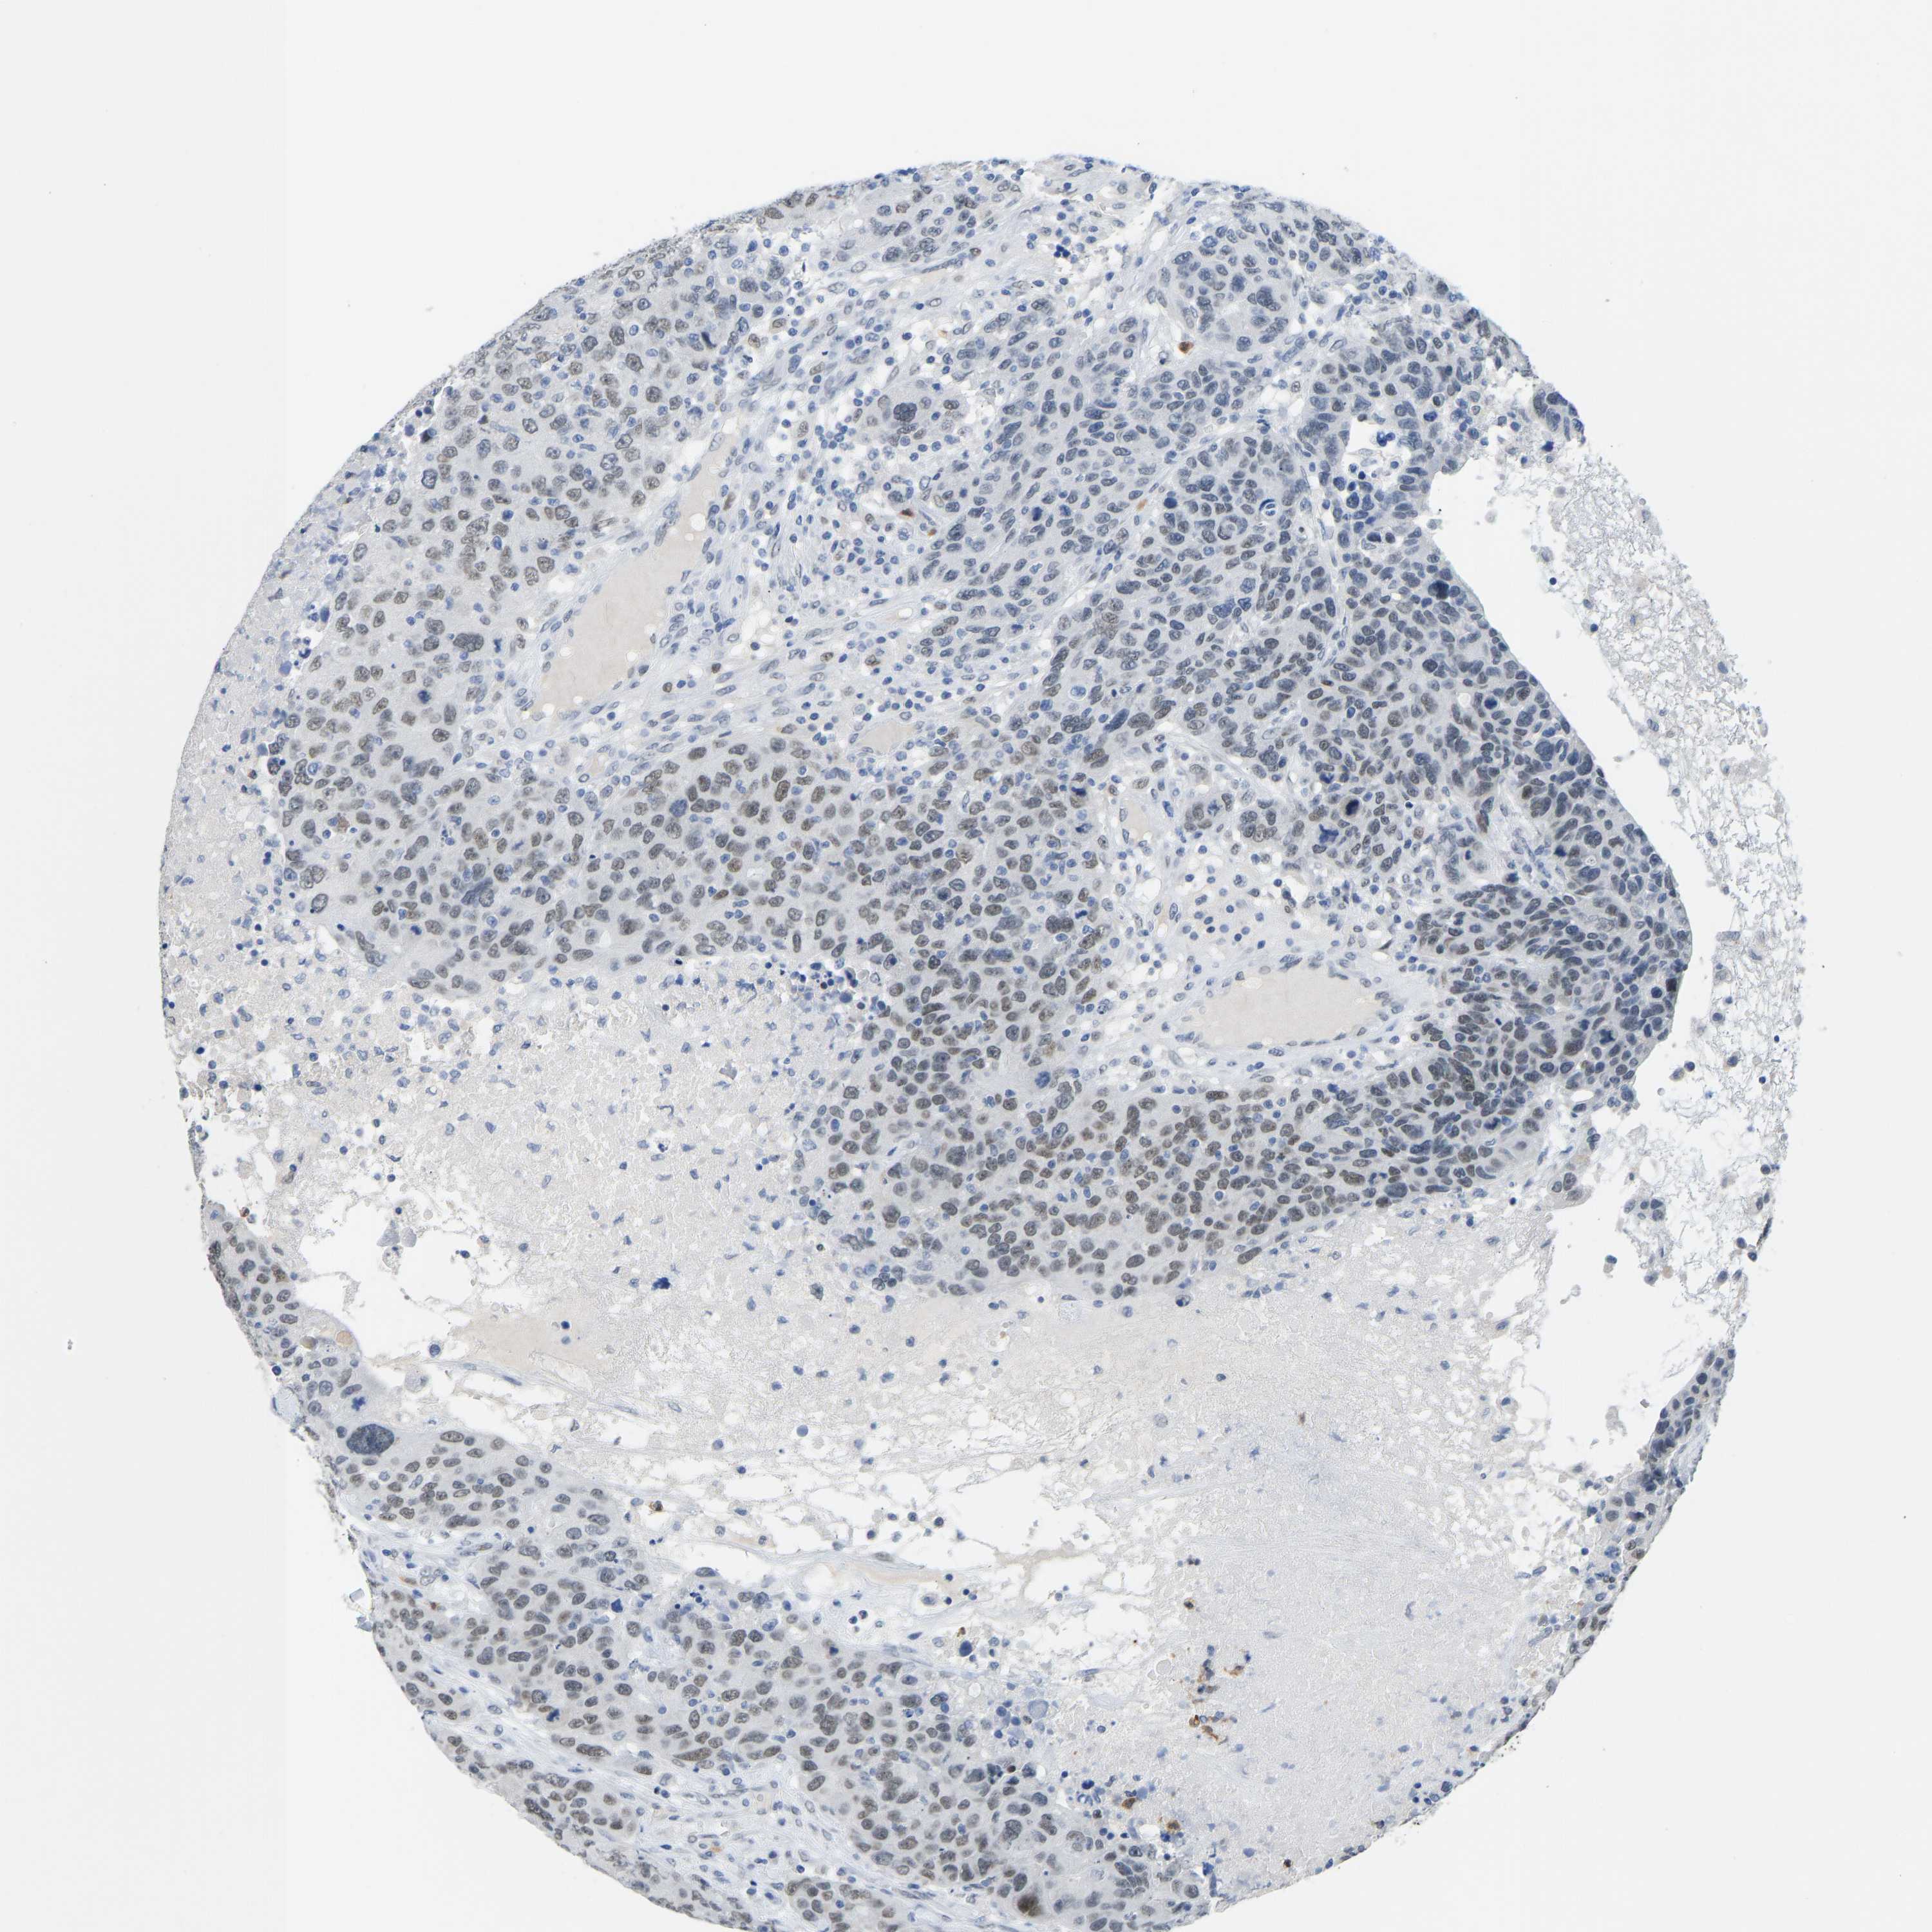

CANCER BREAST CANCER Show tissue menu

BRCA TCGA BRCA VALIDATION PROTEIN EXPRESSION